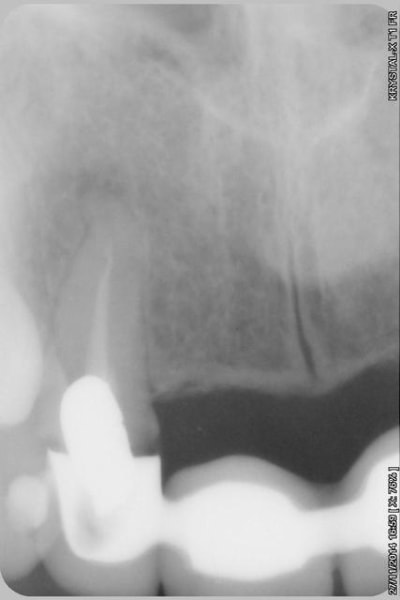

le scan n'est pas terrible, mais suffisant pour voir que 22 une fois extraite, ne va pas etre simple à implanter, par contre 11/21 avec un peu d'expansion...

Donc dans un premier temps,je décide d'essayer de retraiter 12/22, de toute façons ça ne peut pas être pire que ce qui tiens depuis 10 ans... enfin 12 mobilité quasiment 3.

ensuite Srew post (bouh...) et résine, afin de pouvoir poser un provisoire et réfléchir à l'avenir du parodonte...car il va y avoir un problème quelle que soit la solution choisie.